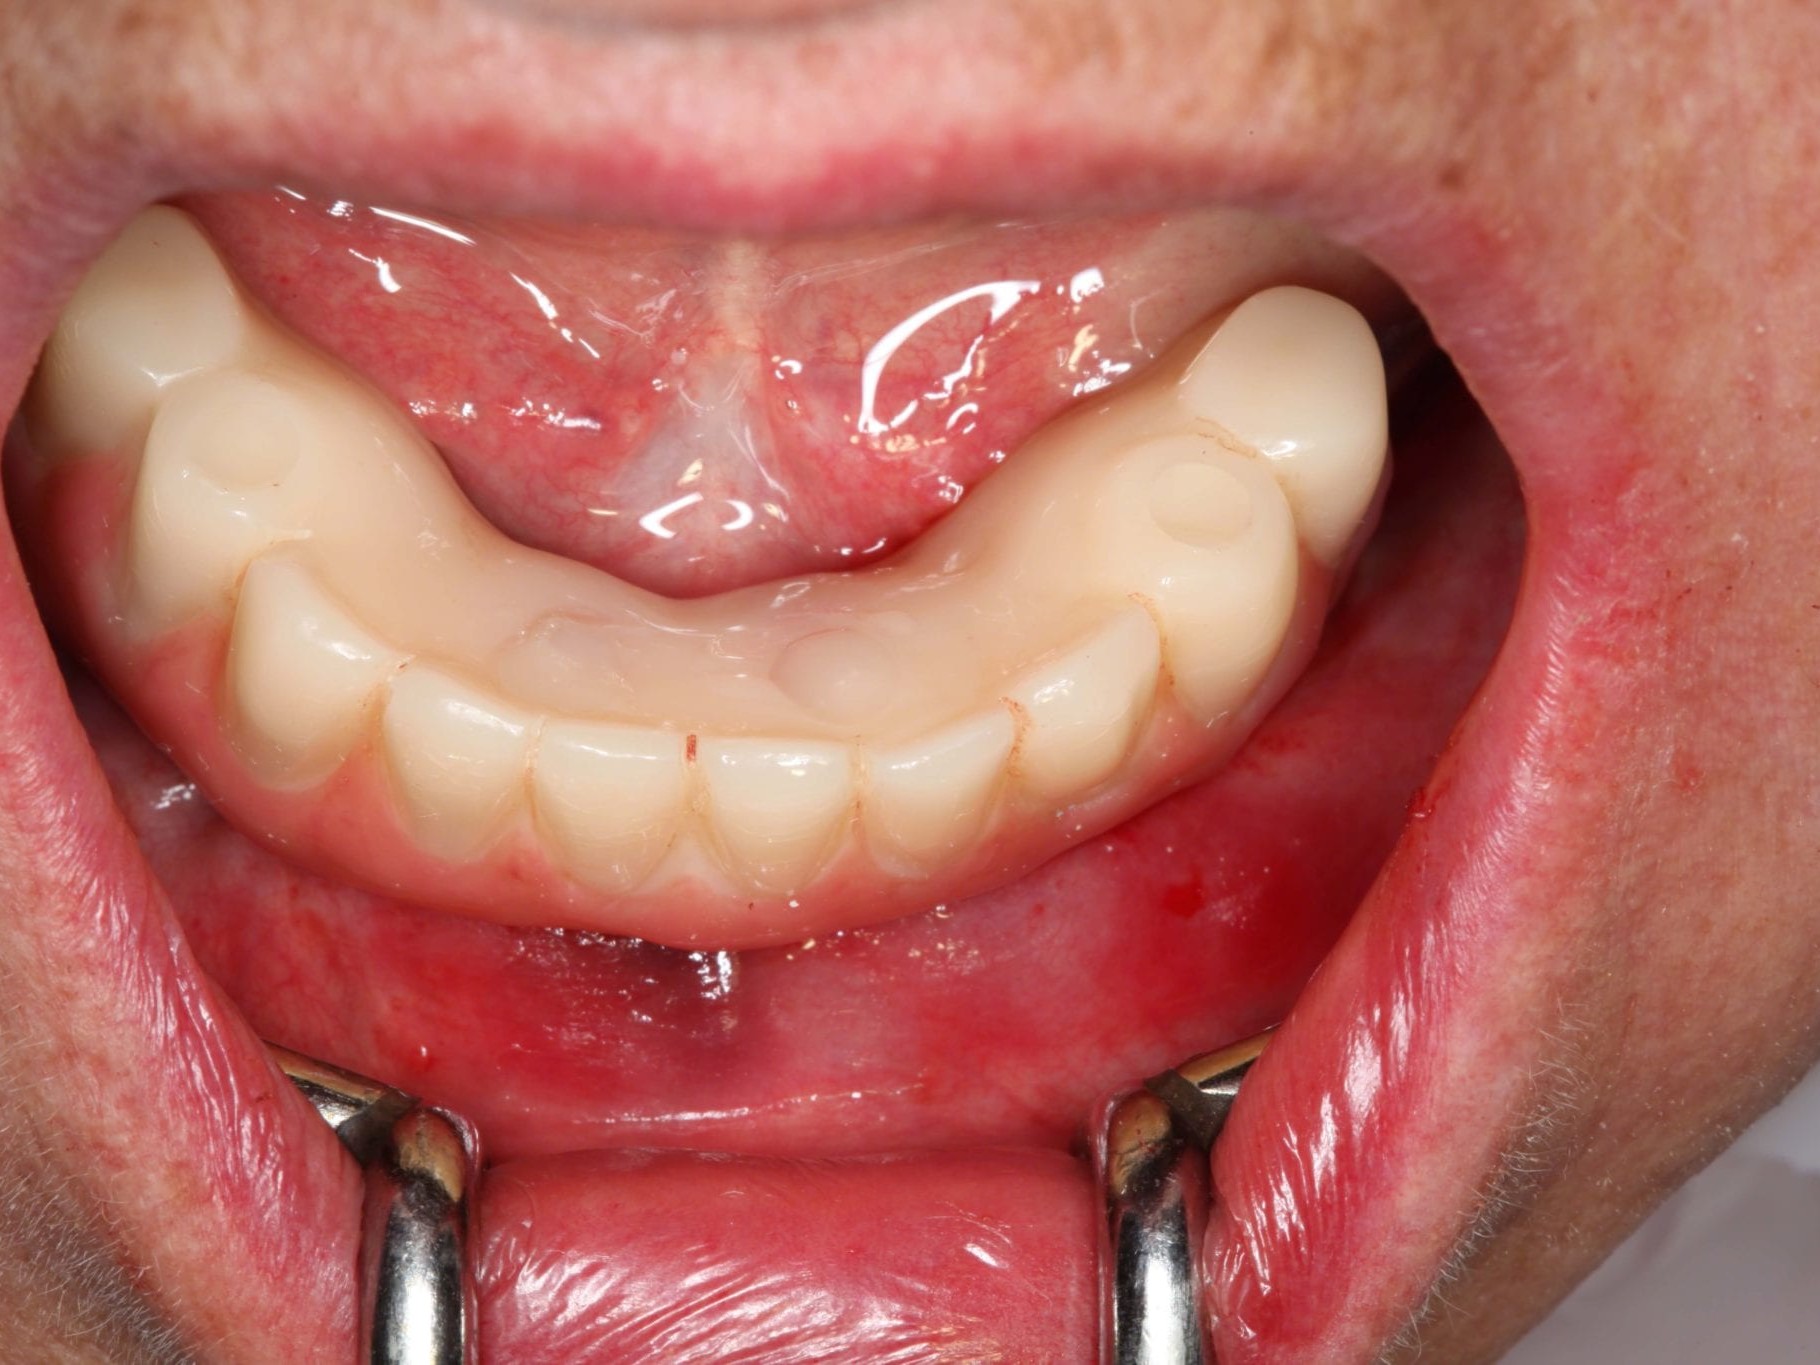

In Lokalanästhesie unter anästhesiologischem Standby mit intravenöser Antibiose mittels Clindamycin 600 mg 2mal/d wurde die Bohrschablone eingesetzt und mit Osteosyntheseschrauben fixiert (Abb. 8). Der Eingriff erfolgte nahezu flapless und somit transgingival. Nun erfolgte die Umsetzung des Straumann Hülse-in-Hülse-Konzeptes. Der Zylinder des Bohrlöffels wird in die an der Bohrschablone fixierten Hülse (Ø 5 mm) in den geplanten Regionen eingeführt. Für jeden Bohrerdurchmesser (Ø 2,2 mm und Ø 2,8 mm) ist ein entsprechender Bohrlöffel erhältlich. Jeder Bohrlöffel besitzt an seinen Enden Zylinder unterschiedlicher Höhe, die entsprechend chirurgischem Protokoll angewendet werden. Es wurden sämtliche Bohrstollen protokollgemäß aufbereitet (Abb. 9-11). Nach der Aufbereitung der Bohrstollen für die angulierten Implantate (Abb. 12-14) wurden die Straumann Bone Level Tapered Implantate (ø 3,3 mm) in regio 035 (Länge 10 mm) und 045 (Länge 12) gesetzt (Abb. 15). Abschließend wurden sämtliche Endpositionen der Implantate in regio 035 und 045 anhand der Lasermarkierungen am Übertragungsteil betreffend ihrer orovestibulären Ausrichtung exakt überprüft (Abb. 16). Nach Entfernung der Einbringhilfen und der Osteosyntheseschrauben konnte die Bohrschablone wieder entnommen werden. In regio 032 und 042 wurden nun die durchmesserreduzierten Straumann NNC (ø 3,3 mm Länge 12 mm) Implantate inseriert (Abb. 17, 18). Bei diesen Implantaten bedurfte es keiner Ausrichtung bezogen auf die orofasziale Ausrichtung. Hier musste die Insertionstiefe bezogen auf das NNC-Implantat beachtet werden (Abb. 19). Die NNC-Implantate wurden mit den entsprechenden Klebebasen versehen (Abb. 20). Danach wurden in regio 035 und 045 auf die Pro Arch Sekundärteile die dazugehörigen Retentionskappen (Abb. 21), die zur Vergrößerung der Oberfläche mit 120 μ Aluminiumoxyd abgestrahlt wurden, eingesetzt. Es erfolgte der typische Naht-Wund-Verschluss mit Einzelknopfnähten. Zum Abschluss erfolgte das prothetische Procedere mit der Eingliederung des Interimszahnersatzes in Okklusion (Abb. 22). Hierfür wurden die Retentionskappen und die Klebebasen mit dem Sofortprovisorium über ein selbsthärtendes fluoreszierendes kaltpolymerisierendes Paste-Paste-Kartuschensystem fixiert, dieser Zahnersatz extraoral versäubert (Abb. 23) und in der Mundhöhle refixiert (Abb. 24). Die Schraubenkanäle wurden mit Kunststoff verschlossen (Abb. 25). Abschließend erfolgte die radiologische Kontrolluntersuchung (Abb. 26).